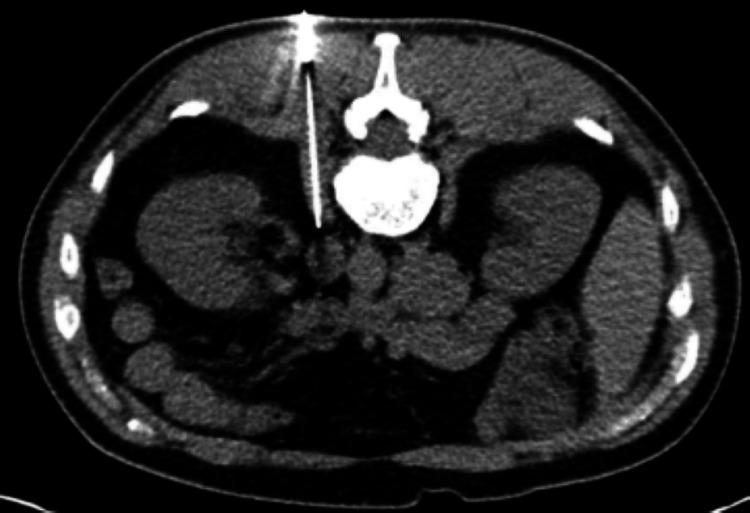

Lung cancer remains the leading cause of cancer-related deaths globally. While smoking-related lung cancers still account for most cases and cause approximately 100,000 deaths annually in the USA, smoking rates have been declining for decades. Lung cancer in never-smokers (LCINS), which tends to affect women and Asian populations, is now the fifth most common cause of cancer-related deaths worldwide. In 2023, over 20,000 lung cancer deaths in the USA were projected to occur in never-smokers, making LCINS the eighth leading cause of cancer-related mortality in the country. As the number of LCINS cases rises, it becomes increasingly important to explore the unique causes and characteristics of the disease, which calls for tailored diagnostic approaches and personalized treatment plans. Lung adenocarcinoma (LUAD) can present with atypical imaging features that often resemble benign conditions, including pneumonia, lung abscesses, post-infectious scarring, atelectasis, mediastinal masses, emphysema, and granulomatous disease. This variability in presentation can hinder accurate diagnosis and potentially delay timely treatment. While lung cancer is uncommon in younger individuals, with only 5.6% of new cases occurring in those under 54 years old, clinicians should maintain a high index of suspicion, as early detection is essential, and atypical cases can be easily missed. Here, we present a complex case involving an unusual radiologic manifestation of a lung mass, in which tuberculosis was initially considered the primary differential diagnosis.

肺癌仍然是全球癌症相关死亡的主要原因。虽然与吸烟相关的肺癌仍然占大多数病例,并且在美国每年导致约10万例死亡,但吸烟率几十年来一直在下降。从不吸烟者中的肺癌(LCINS),往往影响女性和亚洲人群,现在是全球癌症相关死亡的第五大常见原因。2023年,预计美国超过2万例肺癌死亡将发生在从不吸烟者中,使LCINS成为该国癌症相关死亡率的第八大原因。随着LCINS病例数量的增加,探索该疾病的独特病因和特征变得越来越重要,这需要量身定制的诊断方法和个性化的治疗方案。肺腺癌(LUAD)可能表现出非典型的影像学特征,这些特征通常类似于良性疾病,包括肺炎、肺脓肿、感染后瘢痕、肺不张、纵隔肿块、肺气肿和肉芽肿性疾病。这种表现的变异性可能会阻碍准确诊断并可能延迟及时治疗。虽然肺癌在年轻人中并不常见,只有5.6%的新病例发生在54岁以下的人群中,但临床医生应保持高度的怀疑指数,因为早期检测至关重要,非典型病例很容易被漏诊。在此,我们介绍一个复杂病例,涉及肺部肿块的不寻常放射学表现,其中最初将肺结核视为主要鉴别诊断。